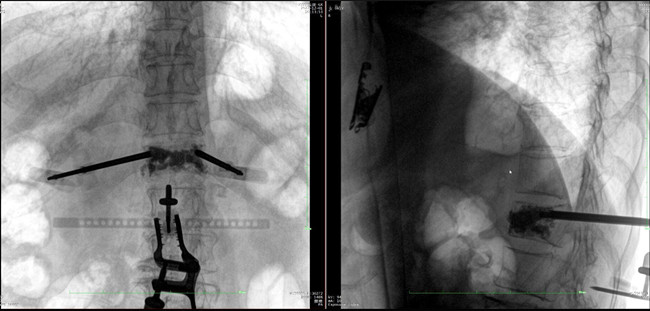

? 手術效果確認

*骨水泥置入效果良好

良好的臨床使用體驗源于普愛醫(yī)療骨科機器人導航系統(tǒng)和醫(yī)生的完美配合。亞毫米級的準確定位、直觀的術前規(guī)劃和機械臂的執(zhí)行,使醫(yī)生無需擴大創(chuàng)口進行傷椎入針路徑定位,僅需術前三維重建即可全方位了解傷椎位置及穿刺路徑,除了極大的提高了一次性穿刺成功率,也大幅降低了手術對醫(yī)生經(jīng)驗的要求,手術上手難度更低。